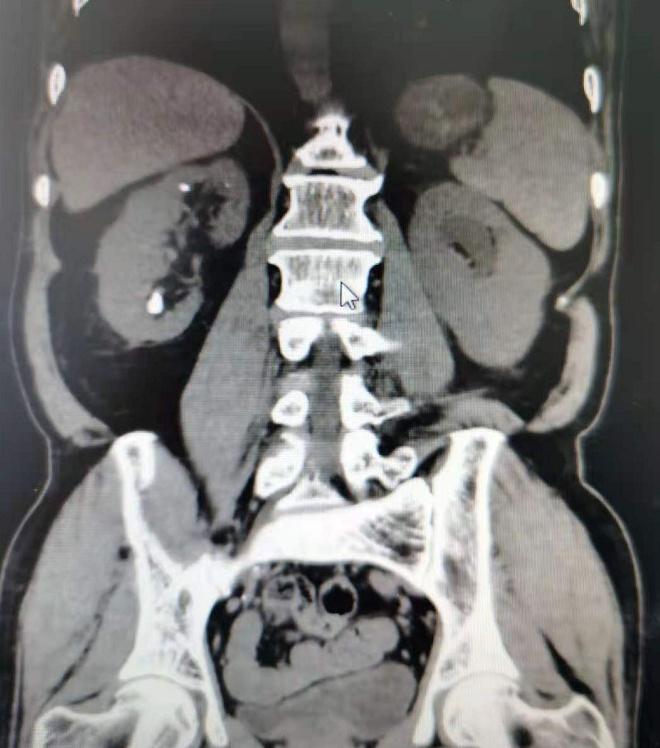

术前CT平扫提示右肾下盏结石

此例患者为男性,65岁,BMI:24.3kg/m2,主因“肾下盏结石”收住入院,结石位于肾下盏前组盏,结石大小约为1.2X1.5cm,CT值为1532HU,该病例入院后,经泌尿外科三病区主任包军胜、主任医师左陵君、副主任医师何綦琪综合考虑评估后,采用了新技术超微经皮肾镜碎石取石术(SMP)进行手术治疗。